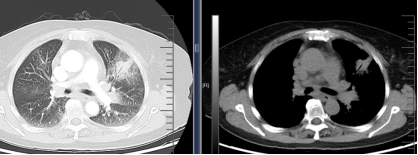

在充分术前评估及沟通后,由呼吸介入团队张海涛副主任为刘阿姨施行R-EBUS引导下的肺活检术。首先通过高分辨率CT及三维重建技术精准规划进镜路径,确定病灶位于左肺上叶前段(图1)。术中,张主任操作超声探头沿目标支气管逐步推进,在实时超声监测下清晰捕捉到软组织回声信号(图2),确认定位后迅速而稳妥地完成活检取样。病理结果回报为肺腺癌(图3),至此,刘阿姨的病情终于真相大白了,为后续全身治疗提供了坚实依据。

图1 胸部CT提示:左肺上叶阴影。